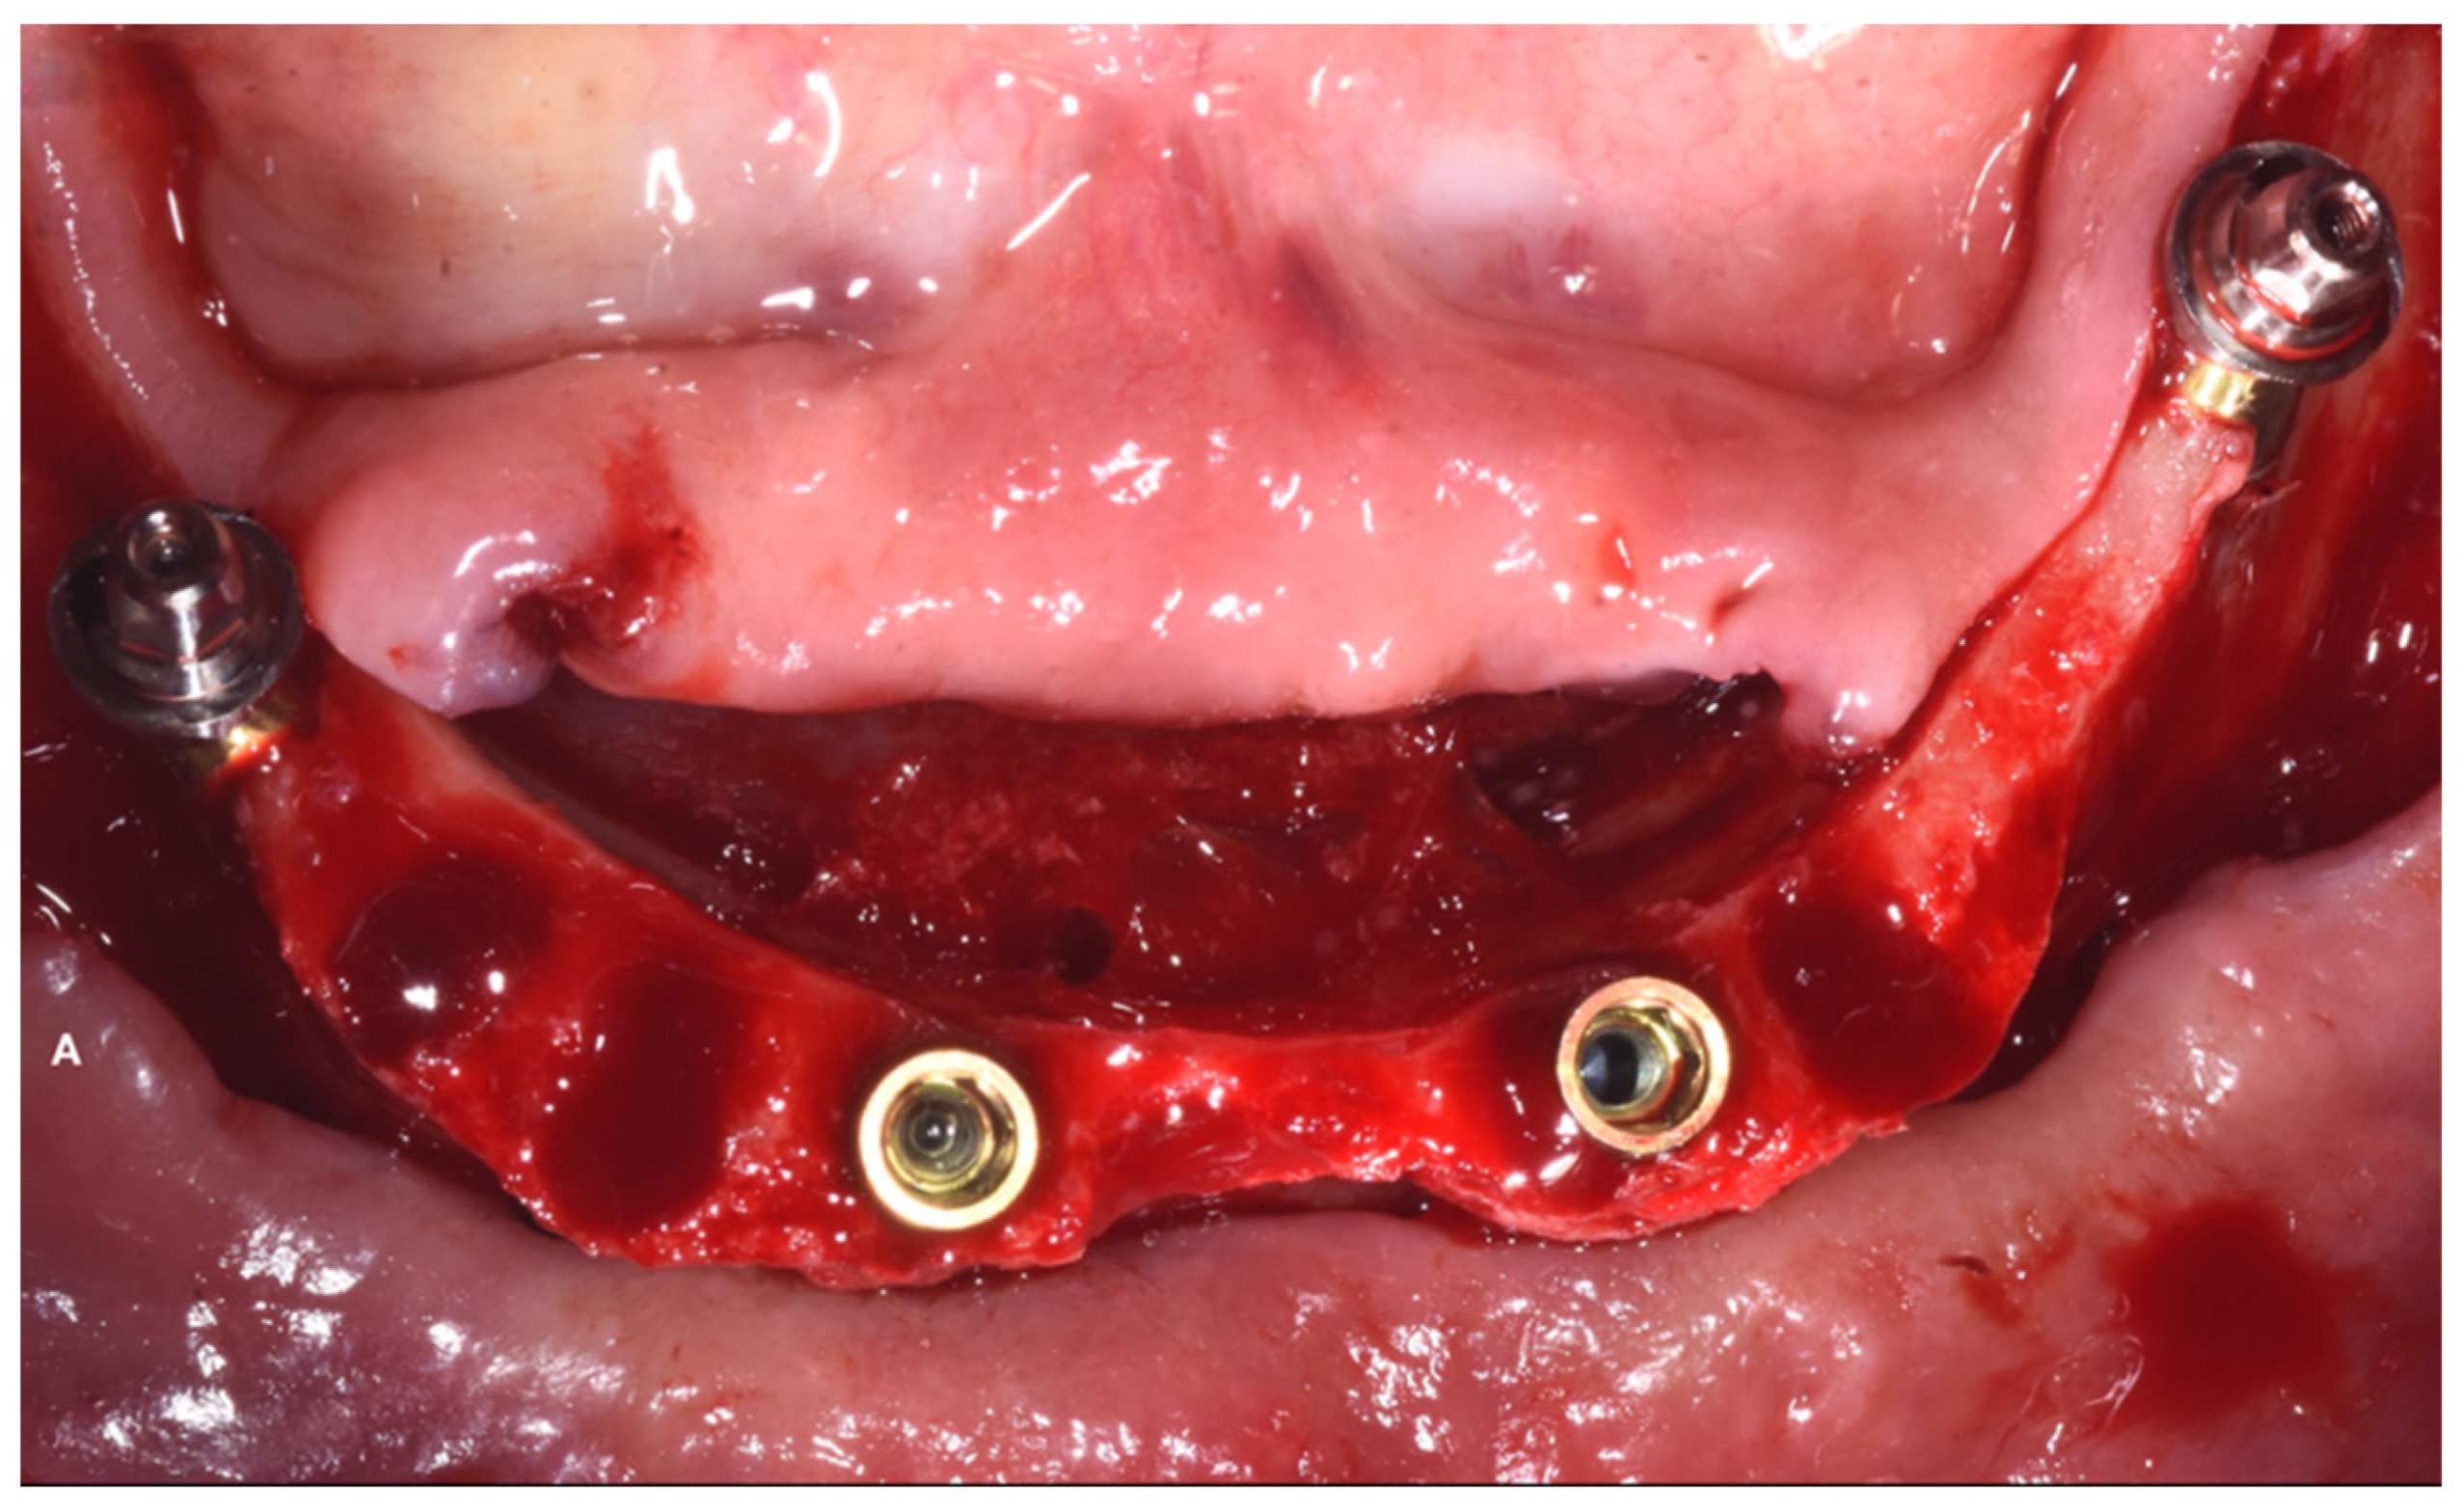

2. Case Report

Surgery Appointment